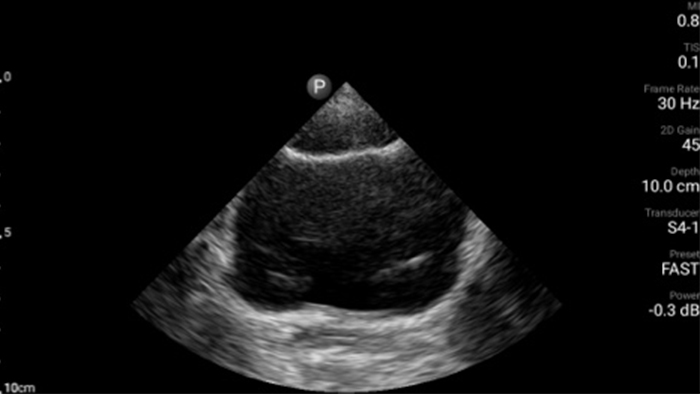

Lumify handheld ultrasound offers images that enhance diagnostic confidence.

See more when it counts

Lumify can help you make real-time decisions with more confidence, from assessment to recovery. Reveal the subtle details of an image, uncover enriched tissue definition with multiple angles and much more.